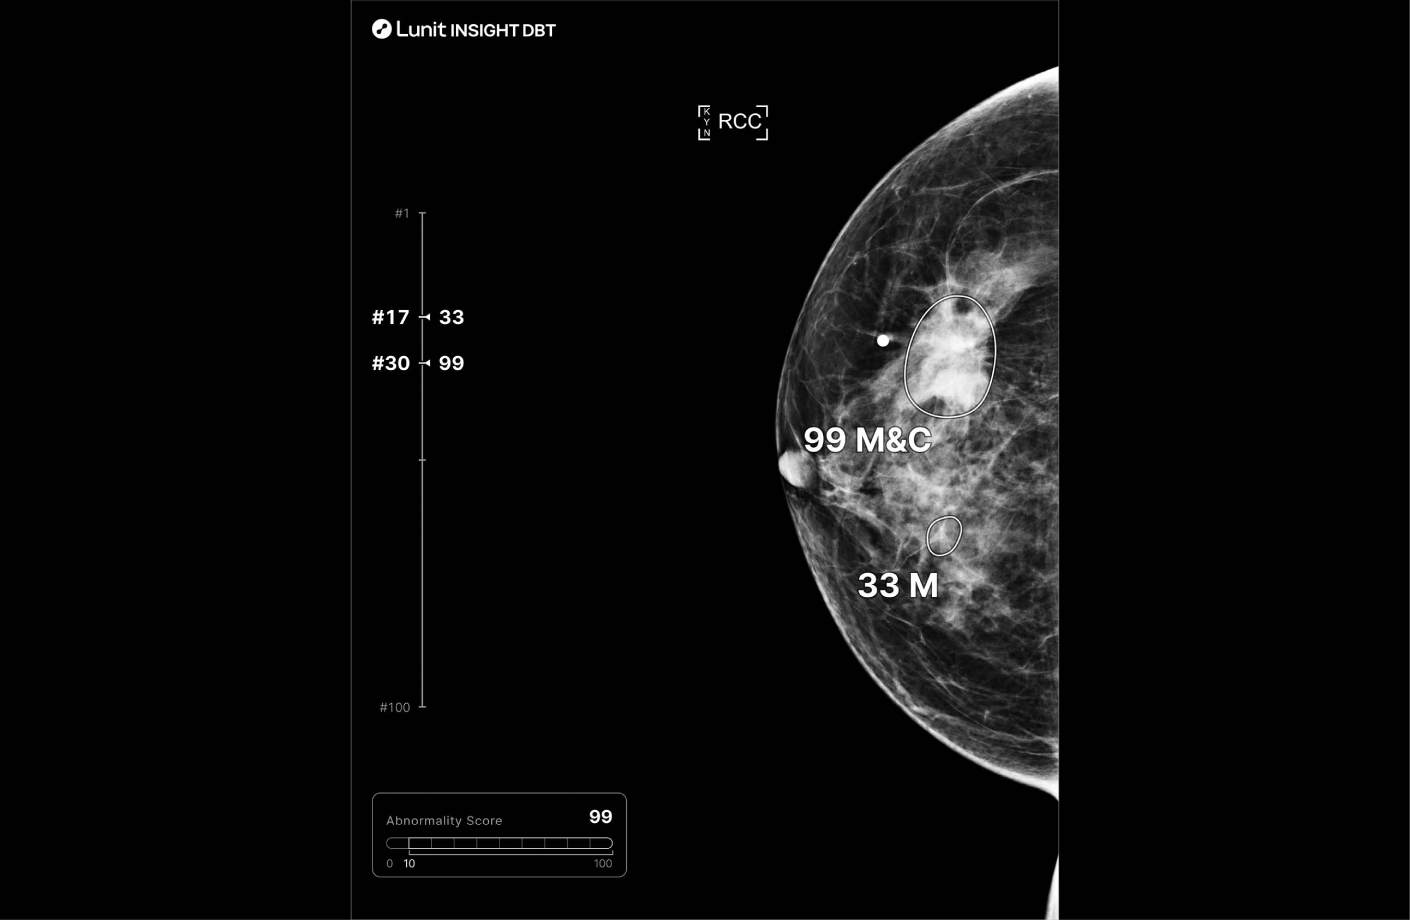

루닛 인사이트 DBT는 유방단층 촬영 영상을 분석해 유방암 의심부위의 위치와 유방 내 병변이 존재할 가능성을 0~100 범위의 점수로 표시합니다.

또한 병변 유형을 세 가지로 표시합니다.

• Soft tissue (M): Mass, Asymmetry, Architectural Distortion

• Calcification (C)

• Soft tissue with Calcification (M&C)

분석결과는 별도 생성되는 영상 혹은 원본 영상 위에서 확인할 수 있습니다.

루닛 인사이트 DBT는 별도의 이미지 위에 병변이 검출된 슬라이스의 번호와 병변 점수를 표시합니다. 이를 먼저 확인 후 해당 슬라이스로 이동해 판독 할 수 있습니다.

Annotated mammogram showing AI-assisted mammography highlighting lesions with heatmaps and malignancy scores for diagnostic decision support.